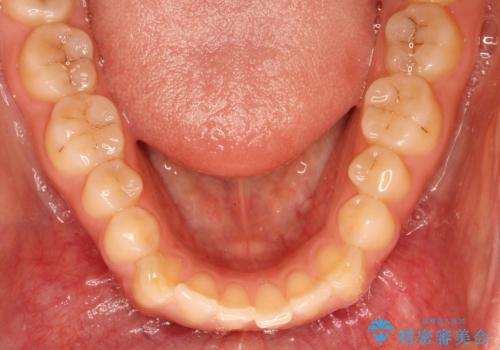

上下の前歯が当たらない インビザラインによる開咬の矯正治療

- 上下の前歯の間に隙間があるとのことで来院されました。

開咬とよばれる、奥歯しか上下の歯が接触していない状態でした。

使用時間を守っていただけたので、比較的スムーズに矯正を終了することができました。

前歯で物が咬み切れるようになり、喜んでいただけました。